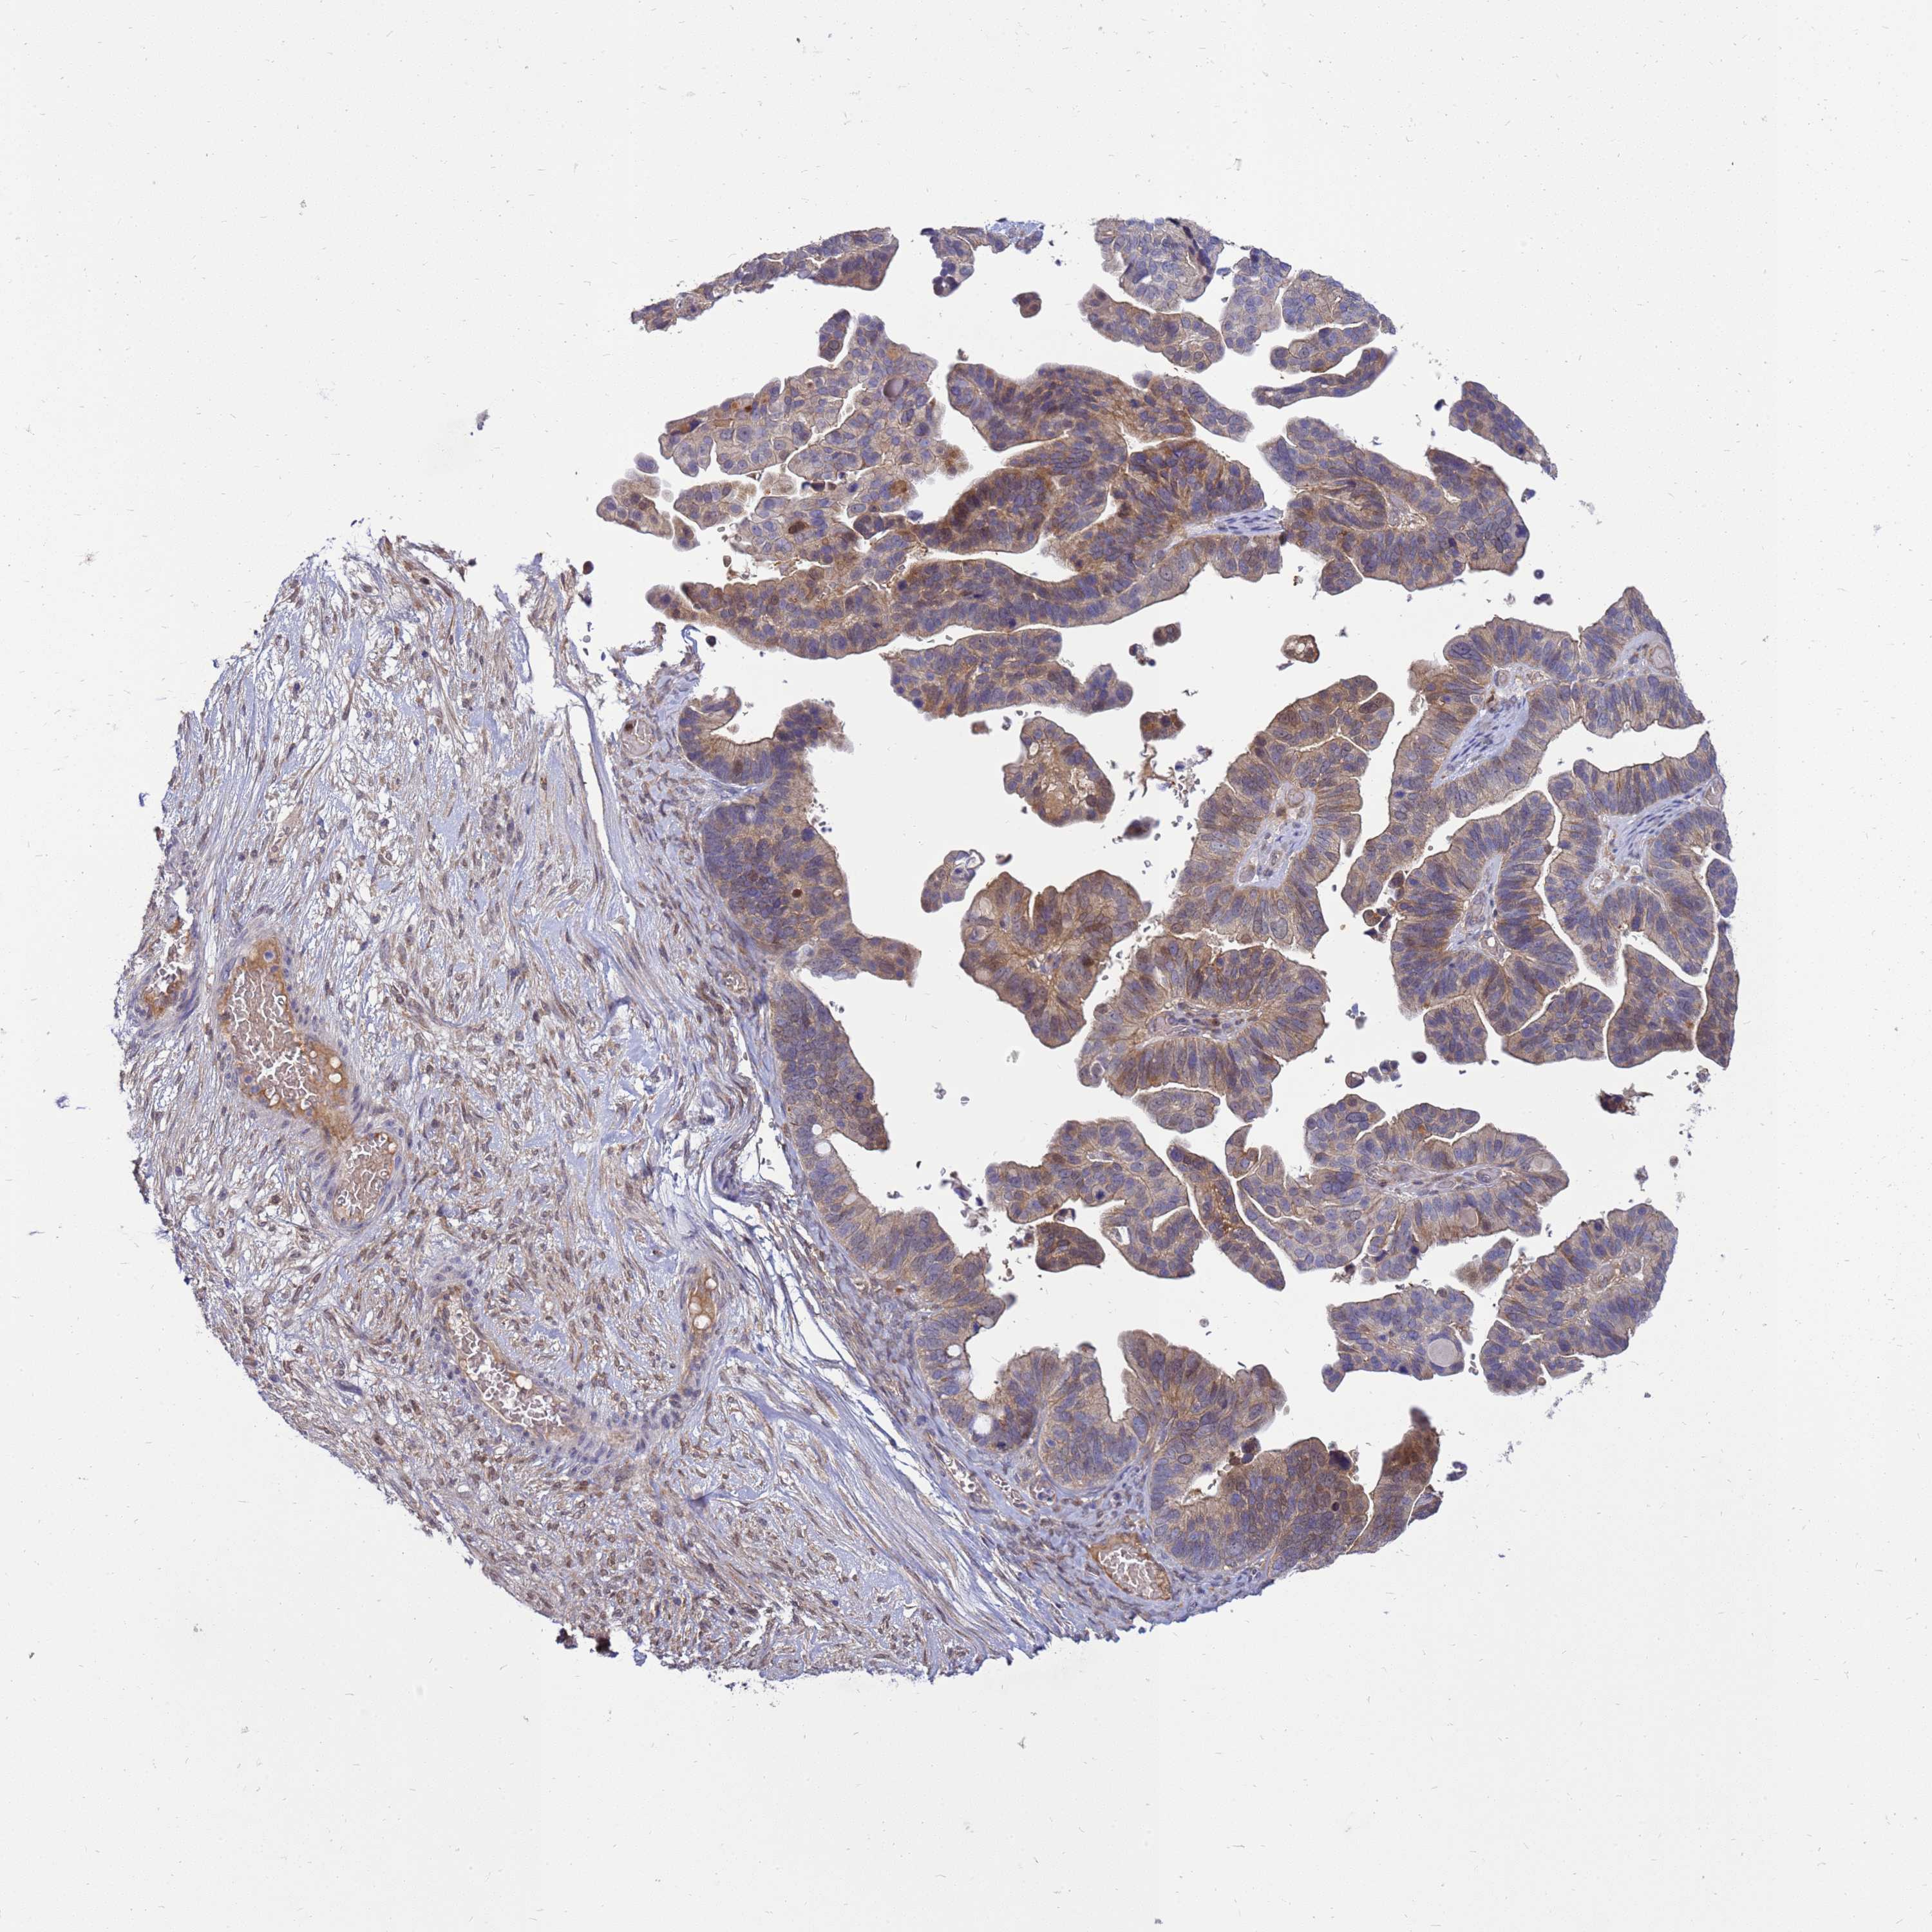

OVARIAN CANCER - Protein expressioni

A mouse-over function shows sample information and annotation data. Click on an image to view it in a full screen mode. Samples can be filtered based on level of antibody staining by selecting one or several of the following categories: high, medium, low and not detected. The assay and annotation is described here.

Note that samples used for immunohistochemistry by the Human Protein Atlas do not correspond to samples in the TCGA dataset.

Antibody stainingi

Antibody staining in the annotated cell types in the current human tissue is reported as not detected, low, medium, or high, based on conventional immunohistochemistry profiling in selected tissues. This score is based on the combination of the staining intensity and fraction of stained cells.

Each image is clickable and will lead to virtual microscopy that enables deeper exploration of all samples and also displays staining intensity scores, fraction scores and subcellular localization as well as patient and tissue information for each sample.

Antibody HPA045537

Staining

High

Medium

Low

Not detected

Intensity

Strong

Moderate

Weak

Negative

Quantity

>75%

75%-25%

<25%

None

Location

Nuclear

Cytoplasmic/membranous

Cytoplasmic/membranous,nuclear

Cystadenocarcinoma, serous, NOS

Carcinoma, NOS

Cystadenocarcinoma, mucinous, NOS

Carcinoma, endometroid